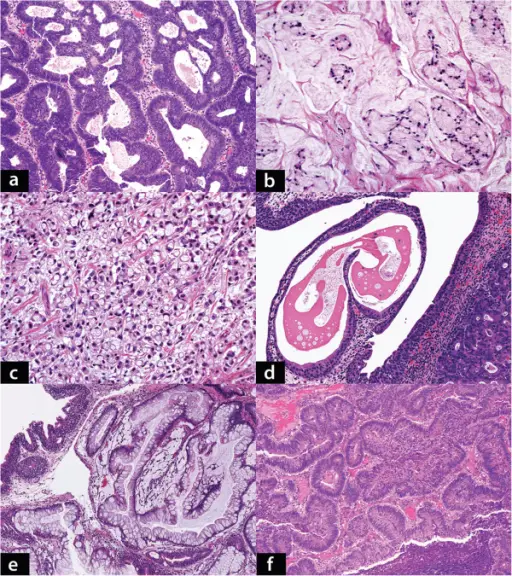

Urothelial Carcinoma

Urothelial carcinoma is also known as transitional cell carcinoma.

The epithelial lining of the renal pelvis, ureter, bladder, or urethra is the source of this malignant tumor.

Urothelial carcinoma is the most typical type of bladder cancer.

Risk factors for urothelial carcinoma include:

- Cigarette smoke (major risk factor)

- Naphthylamine

- Azo dyes

- Cyclophosphamide

- Phenacetin

The typical presentation of urothelial carcinoma is painless hematuria in an adult.

Urothelial carcinoma arises via two distinct pathways:

- Flat

- Papillary

Flat urothelial carcinoma is characterized by the invasion of a high-grade flat tumor and is associated with p53 early mutations.

Papillary urothelial carcinoma initially appears as a low-grade papillary tumor, advances to a high-grade papillary tumor, then invades, and is not linked to early p53 mutations.

A field defect is when a tumor recurs and is frequently multifocal in nature.

Squamous Cell Carcinoma of the Bladder

The second most prevalent type of bladder cancer is squamous cell carcinoma (SCC) of the bladder.

Squamous cell carcinoma (SCC) of the bladder is characterized by abnormal, accelerated squamous cell proliferation.

The normal bladder surface is not coated with squamous epithelium, hence this cancer develops against a backdrop of squamous metaplasia.

Symptoms of squamous cell carcinoma (SCC) of the bladder include:

- Chronic cystitis in older women

- Infection with Schistosoma haematobium in Egyptian males

- Persistent nephrolithiasis

Adenocarcinoma of the Bladder

Adenocarcinoma of the bladder is a type of bladder cancer due to malignant glandular cells.

Adenocarcinoma of the bladder may arise from:

- Cystitis glandularis

- Exstrophy

Cystitis glandularis is associated with a urachal remnant and causes adenocarcinoma of the bladder that develops near the dome of the bladder.

Exstrophy is a congenital failure to form the caudal portion of the anterior abdominal and bladder walls.